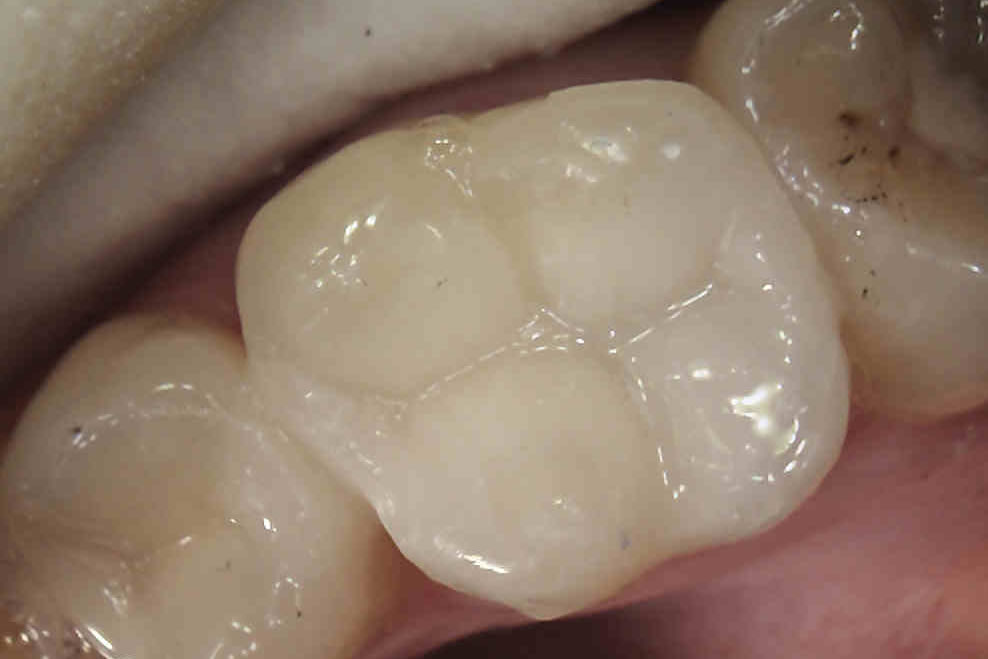

A white filling is a composite material made up of resin and glass, which is a tooth coloured and mercury free and can be used for many different purposes.

If you have a broken or decayed tooth, a composite filling can be used to restore the tooth to its original shape and colour.

Composite fillings can also be used for cosmetic purposes to restore chipped or uneven front teeth. Many patients also opt to have composite fillings used to replace old, unsightly silver fillings.